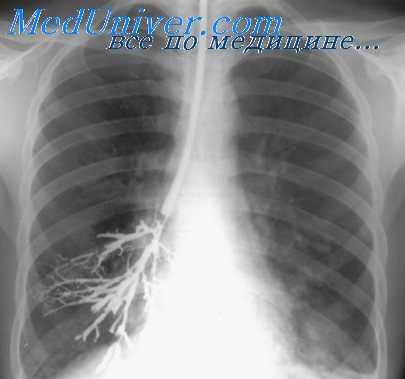

В случае необходимости проводятся совместно два исследования - бронхоскопия и бронхография. Бронхография – рентгенографический метод, при котором в дыхательные пути через катетер или фибробронхоскоп вводится контрастное вещество. Исследование позволяет подробно изучить строение бронхиального дерева (особенно тех его отделов, которые недоступны для эндоскопического исследования) и оценить его двигательную функцию при дыхании.

Бронхография и бронхоскопия. Медиастиноскопия

Бронхографии относится к важным и достаточно сложным методам специальной диагностики. Чаще всего ее производит под местной анестезией, реже прибегают к наркозу (преимущественно у детей). Через катетер в бронхи исследуемого легкого вводит контрастное вещество (масляные или водные препараты йода), которое позволяет получить контуры трахеобронхиального дерева и виутрилегочных полостей.

В настоящее время к бронхографии прибегают при подозрении на бронхоэктазы, внутрилегочные полости, рубцовый стеноз бронха. В зависимости от показаний выполняют тотальное или селективное контрастирование. У больных броихоэктазами .следует считать обязательной последовательную двустороннюю бронхографию, так как в 1/3 случаев поражение бывает двусторонним. Перспективным является выполнение бронхограммы на бумаге методом электрореитгенографин.